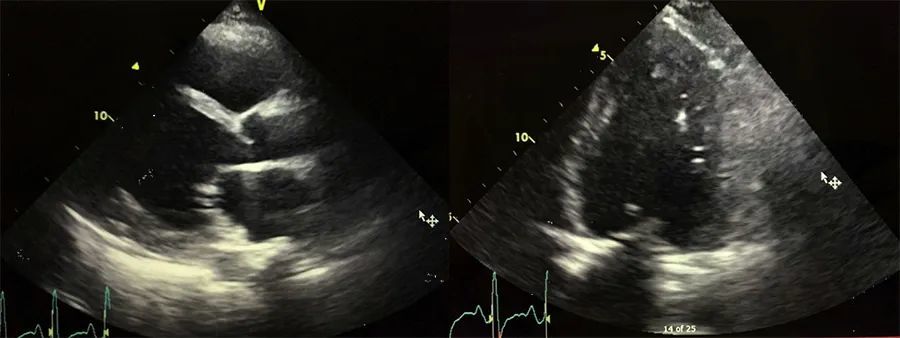

围产期心肌病误诊为扩张型心肌病1例

782x768 - 62KB - JPEG